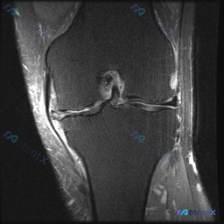

分享一个非常容易踩坑的膝关节MRI读片病例,整理了完整分析思路跟大家一起讨论。 病例影像基本信息 这是一份膝关节MRI T2序列冠状位影像,核心疑问是「观察到Meniscal abnormality(半月板异常)」,我们来一步步拆解分析。 系统阅片结果 按照解剖结构逐一评估: 1. 骨骼关节:股骨远...